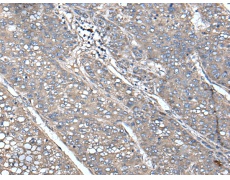

ELISA, IHC |

IHC positive control: |

Human liver cancer and Human lung cancer |

IHC Recommend dilution: |

50-300 |